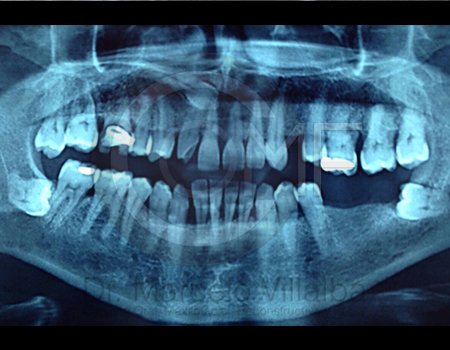

Antes de la extracción se realiza una valoración clínica y estudios de imagen, como radiografías panorámicas o tomografías, para conocer la posición del tercer molar, su relación con los nervios y planificar un procedimiento seguro y adecuado para cada paciente.

No es recomendable. Antes de extraer terceros molares es necesario realizar una valoración clínica y estudios de imagen para conocer la posición del diente, su relación con los nervios y el tipo de procedimiento más seguro para cada paciente.

Algunas extracciones simples de otras piezas dentales pueden ser realizadas por un odontólogo general; sin embargo, por la complejidad que presentan los terceros molares, o si se encuentran retenidos, impactados o cerca de estructuras importantes, se recomienda que el procedimiento sea realizado por un cirujano maxilofacial para mayor seguridad y control del tratamiento.